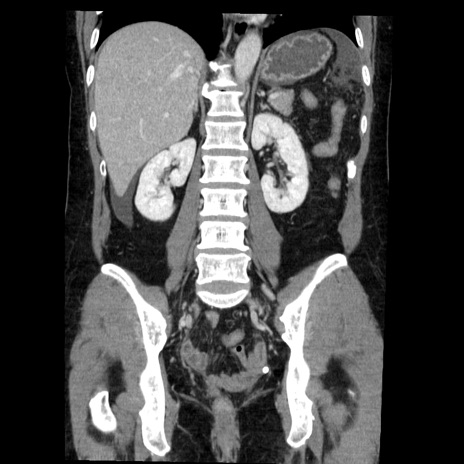

症例6(冠状断像)

【症例】50歳代女性

【主訴】下腹部痛

【現病歴】本日朝より下痢2回あり。 昼食を食べた後、嘔吐3回、下腹部痛認め、症状軽快せず、当院救急搬送。

最終食事:本日昼(生ものなし)。 昨日の夜、刺身を食ぺたとのこと。周囲に同様の症状の者なし。普段、排便は毎日あるとのこと。

【既往歴】卵巣癌術後(8年前に当院で卵巣摘出)

【身体所見】 意識清明、腹部:平坦、腸蠕動音→、やや硬、下腹部自発痛・圧痛あり、反跳痛あり、筋性防御なし。

【データ】WBC 16000、CRP 0.01